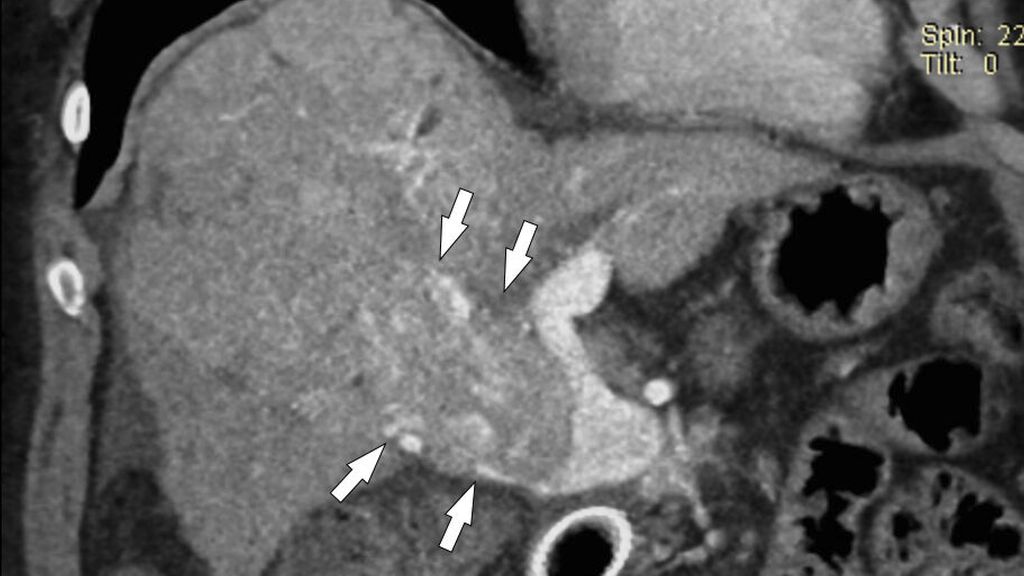

Abb. 6: Pfortader- und Mesenterialvenenthrombose: Die MDCT zeigt die ausgedehnte Thrombose (Pfeile oben) und den ischämischen, wandverdickten Dünndarm (offene Pfeile). In der Laparotomie fand sich eine Dünndarmnekrose

Die am meisten gefürchtete Komplikation bei Ausdehnung der PVT in die Mesenterialvenen ist das Auftreten einer hämorrhagischen Dünndarminfarzierung (Dünndarmnekrose) mit hoher Morbidität und Letalität (Abb. 6). Insgesamt sind bei Verdacht auf das Vorliegen einer Pfortaderthrombose die frühe bildgebende Diagnostik mittels farbcodierter Duplexsonografie und bei inkonklusiver Sonografie eine Kontrastmittel-verstärkte MDCT wichtig für das weitere therapeutische Management.